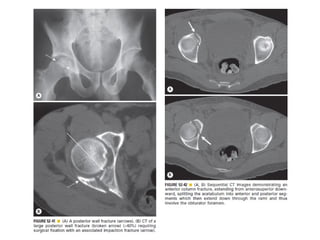

Skeletal trauma was presented by Dr Laith Fadhel with reference to Grainger's Diagnostic Radiology textbook. The presentation covered skeletal trauma as assessed through diagnostic radiology techniques. Key findings and treatments for skeletal injuries were likely discussed.